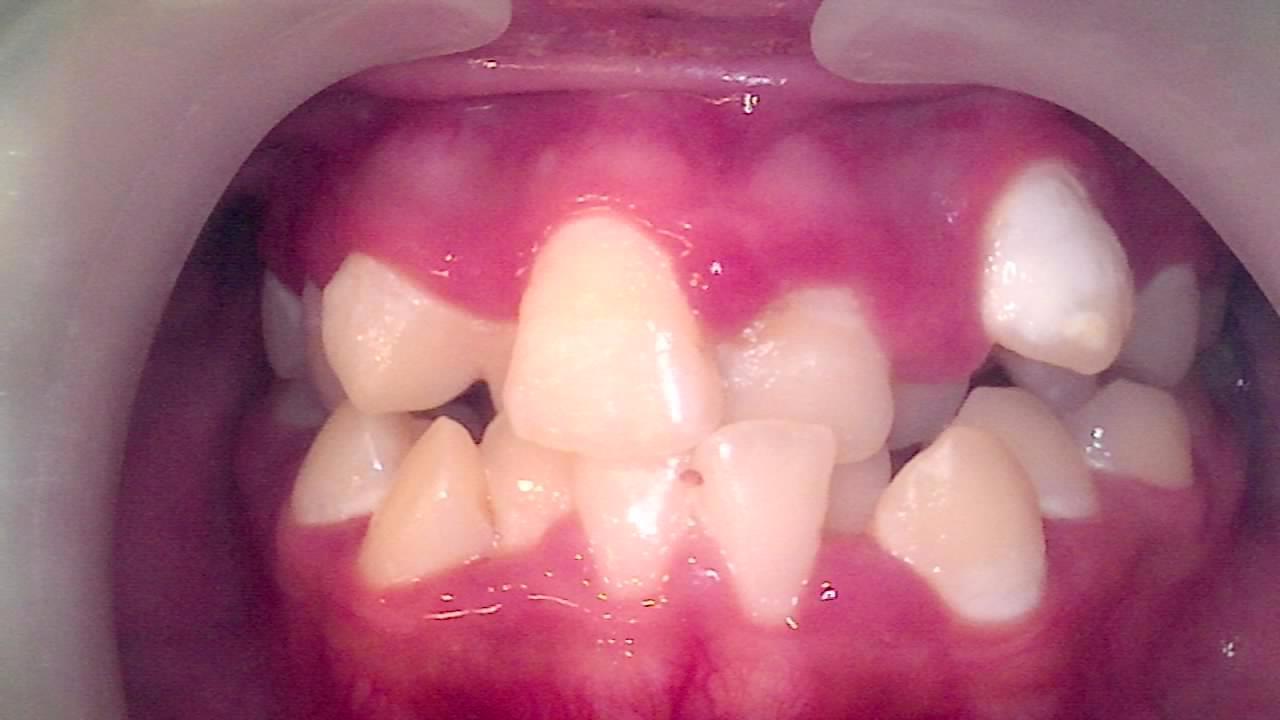

23년 치과의사 생활 중에 top5 안에 들 만큼 치열이 심하게 삐뚤한 아이였어요. 그런데도 1년 전에는 "교정은 하고 싶은데... 치과가 무서워요"라며 계속 망설이더니 결국 치료를 시작하지 않았던 거예요.

1년 전만 해도 간단한 충치치료에다가 교정치료를 바로 시작하면 될 상황이었는데, 지금은 발치해야 할 치아를 결정하고 나머지 24개 치아를 모두 치료한 뒤 교정을 시작해야 하는 상황이 되어버렸습니다.

IC20250823_131114_0278_00013BD6.jpg